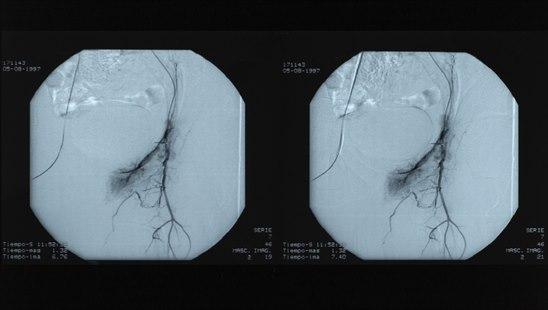

Angiografi som viser trangt parti i arterieAngiografi er en røntgenundersøkelse av blodårer. Større blodårer deles i to grupper:

Angiografi kan derfor grovt inndeles i arteriografi og venografi, avhengig av hvilke kar som undersøkes. For å kunne fremstille en blodåre på røntgen, må det sprøytes kontrastvæske inn i åren. Kontrasten gjør blodåren synlig og man kan granske om det foreligger forandringer i åren.

Undersøkelsen gjør det mulig å påvise skader, forsnevringer, blokkeringer, utposninger (aneurismer) på årene, og viser også blodtilførselen til de organene eller områdene blodårene forsyner.